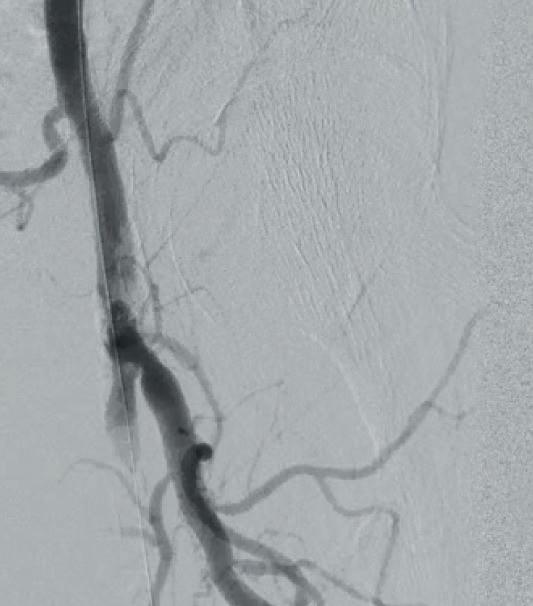

Subsequent diagnostic angiography confirmed the high grade left CFA stenosis (Figure 1) and the long SFA occlusion with diminished contrast flow below the knee. The deep femoral artery showed no significant stenosis within the first centimetres. For

In this case example, a 79-year-old man with severe claudication of the left leg was admitted to our angiology department. Cardiac risk factors included poorly controlled diabetes, renal insufficiency (GFR 27ml/min), severe obesity (body mass index [BMI] 38) and hyperlipoproteinaemia. On duplex ultrasound, a severe calcified short 90% CFA stenosis and a long 30cm occlusion of the superficial femoral artery (SFA) from the origin to popliteal artery (PA) segment one was diagnosed. The posterior tibial artery

recanalization, a crossover approach from the right groin was performed using an 8F crossover Destination reinforced introducer sheath (Terumo). Using an 0.014” Glidewire Advantage guidewire we were easily able to pass the high-grade CFA stenosis with the guidewire.

A 7x60mm IVL catheter was delivered across the lesion and the integrated balloon was expanded to 4atm to facilitate efficient energy transfer. After four calcium modification cycles, we used the integrated balloon to dilate the lesion at 6atm pressure in order to maximize luminal gain. The IVL catheter was then exchanged to an 8x40mm drug-coated balloon (DCB; Lutonix 035

Figure 1

Figure 2